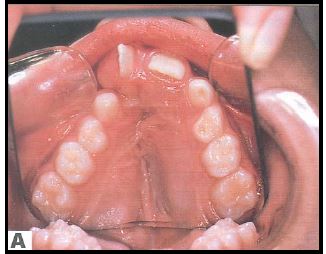

prognaatne hambumus, ülemised eeshambad on ettepoole alumiste suhtes ja eest

progeenne hambumus; alumised eeshambad on ettepoole ülemiste suhtes;

lahihambumus, kui kontaktis on ainult molaarid ehk tagahambad

peetunud lõike- või silmahambad; hambad on küll olemas kuid nad on peetunud

kui puudub lõike- või silmahammas või rohkem kui üks hammas lõualuu ühel poolel